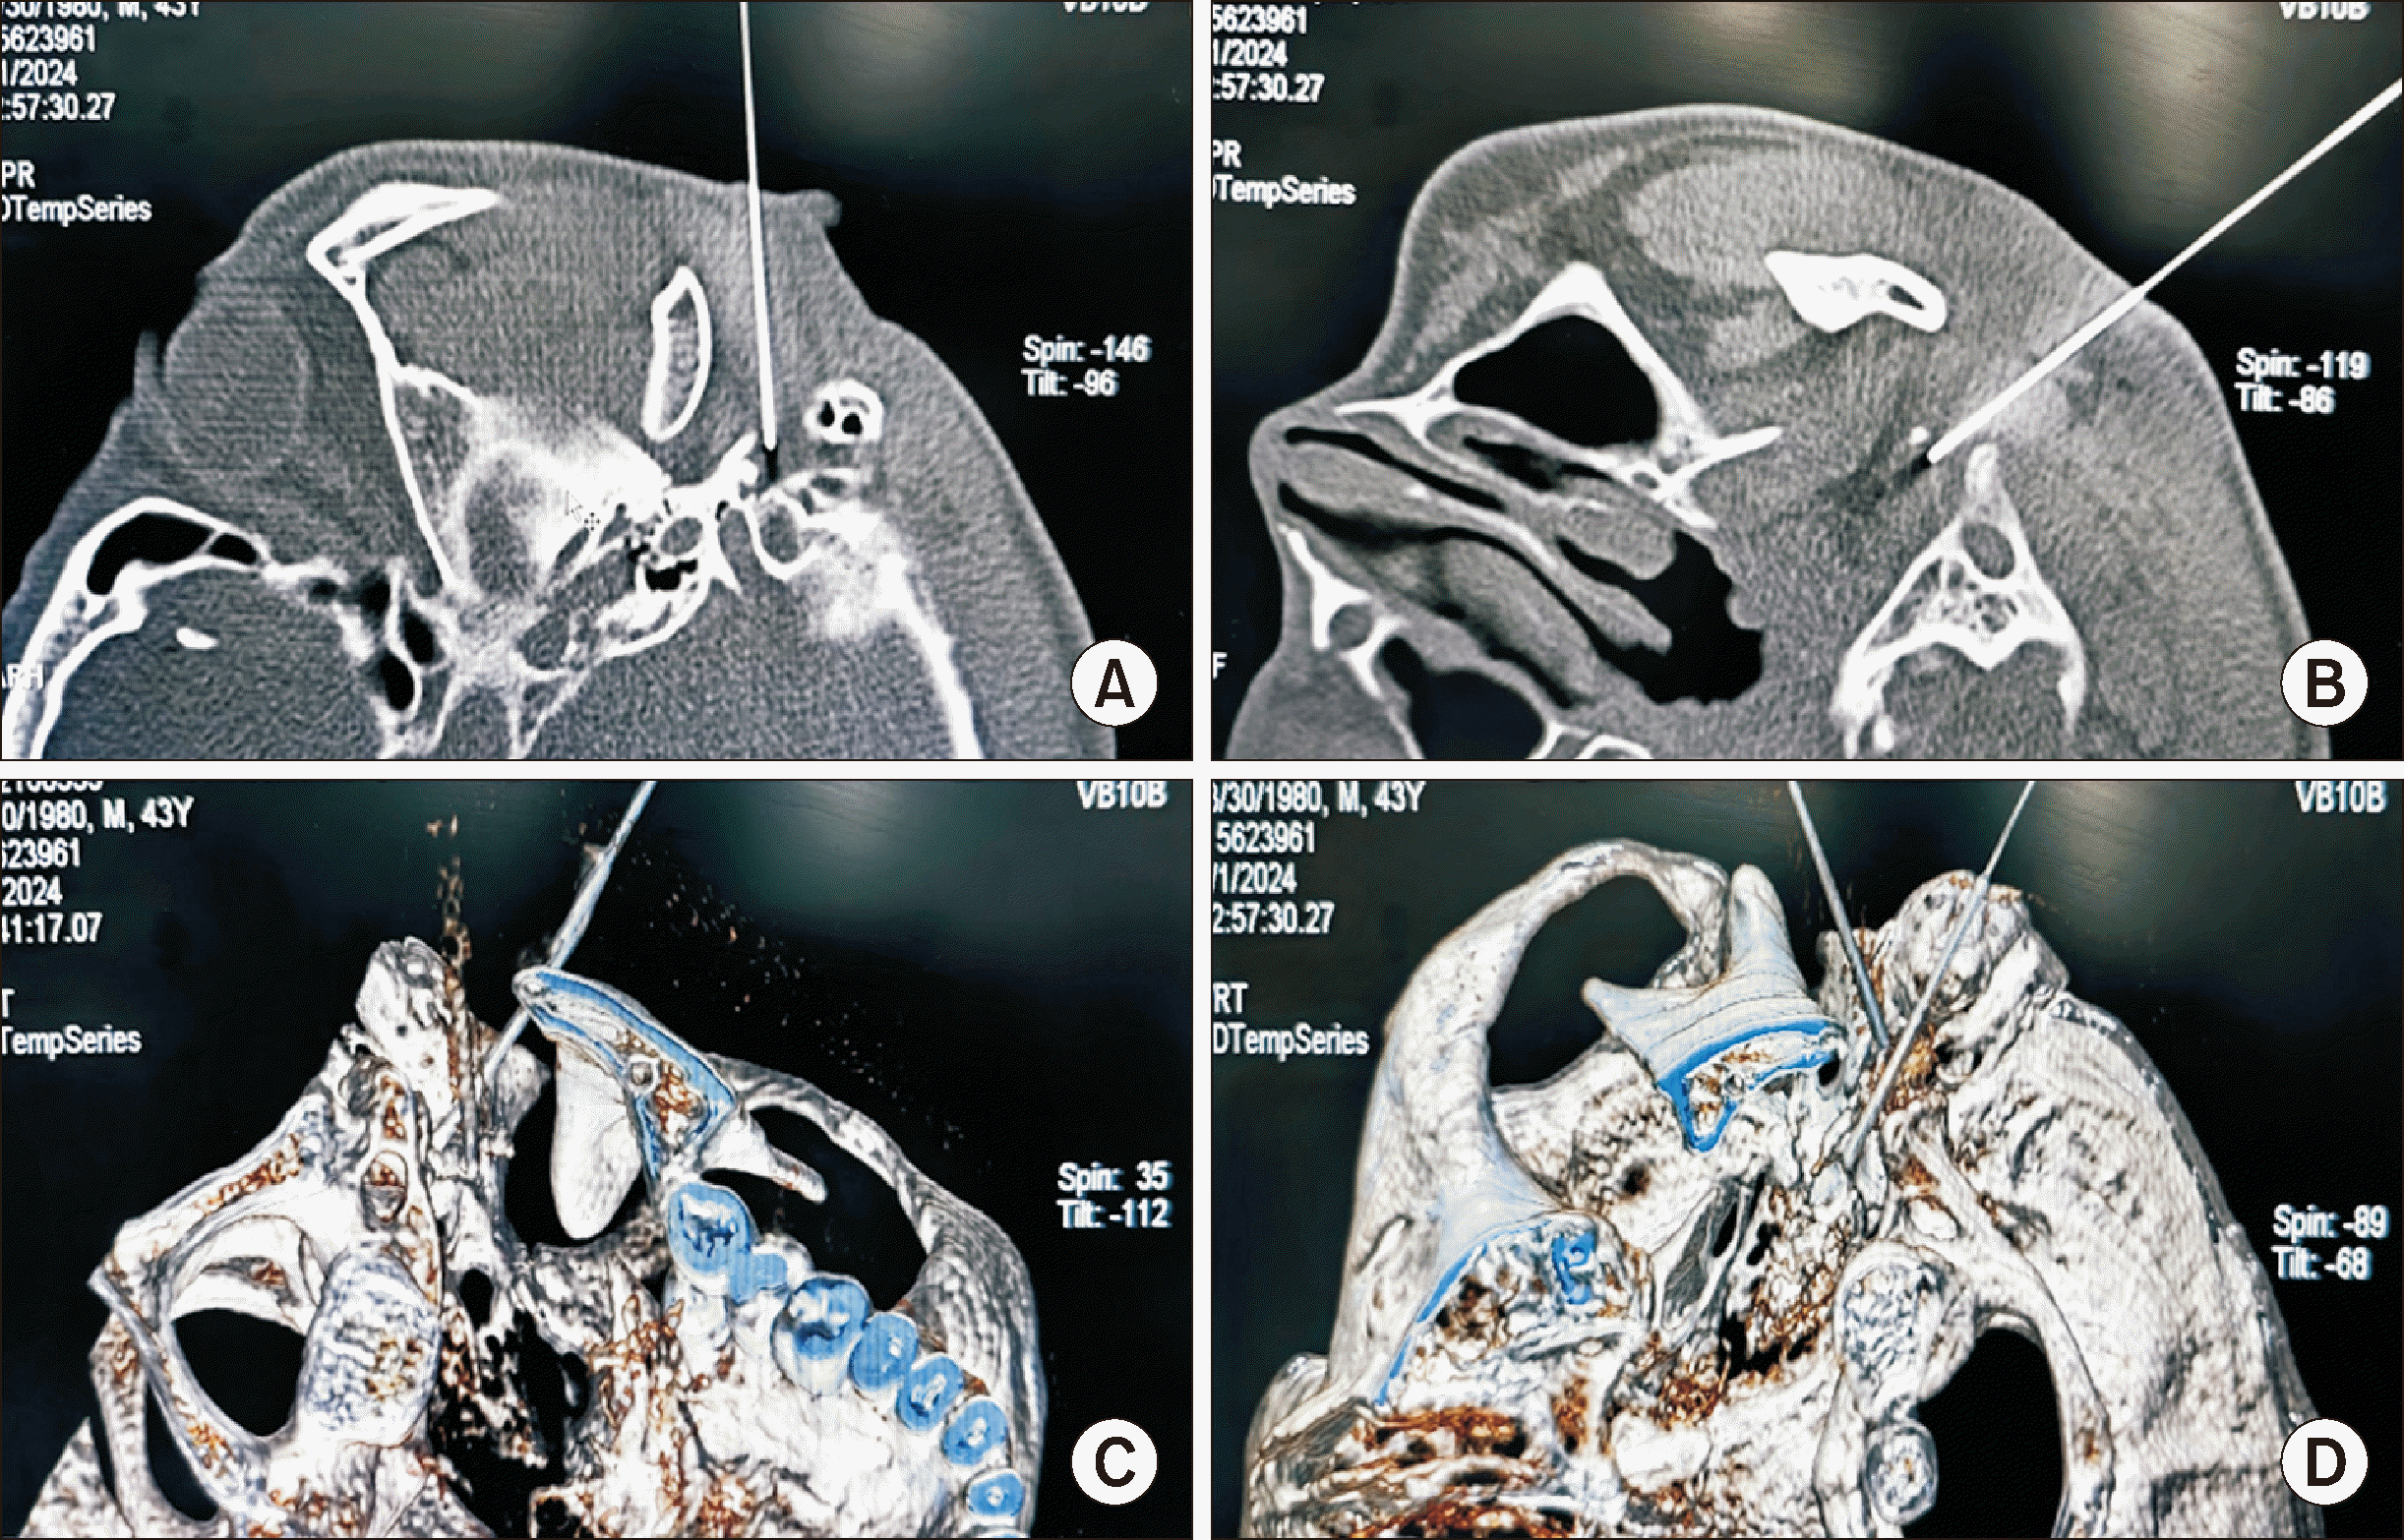

The next day, the patient was placed in the left lateral decubitus position on the CT table, and the right stylomastoid foramen was identified. Afterward, the puncture path was designed with the right stylomastoid foramen and the posterior edge of the styloid process at the level of the upper edge of the right atlas transverse process as targets [4,5], and two radiofrequency needles were inserted to the target according to the designed path (Fig. 2A–C). As anticipated, electrophysiological testing demonstrated that muscles innervated by the facial and accessory nerves displayed rhythmic contraction at the same frequency as the stimulation current. Thereafter, radiofrequency ablation was performed on the right facial nerve at 65°C for 8 seconds, resulting in symptoms of air leakage from the cheek and an inability to fully close the right eye. Subsequently, radiofrequency ablation was conducted on the right accessory nerve at 75°C for 60 seconds [6–8]. Subsequently, the left side was treated in the same way (Fig. 2D).

Fig. 2

(A) CT-guided radiofrequency ablation of facial nerve by right stylomastoid foramen puncture to treat eyelid spasms, lip muscle spasms, or platysma twitches. (B) CT-guided radiofrequency ablation procedure of the accessory nerve by the posterior edge of the styloid process at the level of the upper edge of the right atlas transverse process to treat involuntary head-turning movements. (C) CT three-dimensional reconstruction image after successful puncture of the right facial and accessory nerves with right RF needle points located in the stylomastoid foramen and the posterior edge of the styloid process. (D) CT three-dimensional reconstruction image after successful puncture of the left facial and accessory nerves with left RF needle points located in the stylomastoid foramen and the posterior edge of the styloid process.